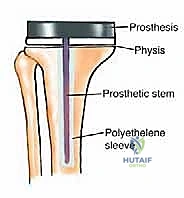

The Biomechanical Imperative of Expandable Implants

The deployment of an expandable endoprosthesis is not merely a geometric exercise in matching bone length; it is a complex biomechanical intervention. The growing skeleton is highly responsive to mechanical loading, governed by Wolff's Law. When a massive metallic implant is introduced, it alters the physiological stress distribution, leading to potential stress shielding, osteolysis, and implant loosening over time. Expandable prostheses must be engineered to mitigate these forces while housing an internal lengthening mechanism—whether mechanical (e.g., minimally invasive worm-drive) or non-invasive (e.g., electromagnetic induction). Furthermore, the fixation of these devices in the pediatric intramedullary canal, which is often narrow and structurally immature, requires specialized techniques, including the use of custom-fluted stems, hydroxyapatite-coated collars for extracortical bone bridging, and precise cementing techniques to ensure long-term survivorship of the construct.

Once the resection level is determined, accurate measured radiographs and MRI cross-sections are transmitted to the prosthesis engineers. They will custom-fabricate or modularly assemble the implant to match the resected bone length precisely, accounting for the required joint line restoration and soft tissue tension. We currently utilize two main categories of expandable prostheses: minimally invasive (mechanical) and non-invasive (electromagnetic).

The Minimally Invasive Expandable Prosthesis (e.g., the JTS implant) is lengthened via an internal worm-drive mechanism. It requires a minor percutaneous procedure where an Allen key is inserted through a small stab incision to manually turn the mechanism. While highly reliable and mechanically robust, it carries a cumulative risk of infection with each lengthening procedure. Conversely, Non-invasive Expandable Prostheses (e.g., Repiphysis or Mutars Xpand) utilize an internal electromagnetic motor driven by an external magnetic coil placed over the limb in the outpatient clinic. This eliminates the need for repeated anesthesia and surgical incisions, drastically reducing the risk of secondary periprosthetic joint infection, though these devices are mechanically more complex and historically prone to internal mechanism failures.

Canal Preparation and Implant Trialing

Following resection, the remaining host bone canal must be prepared. In pediatric patients, the intramedullary canal is often narrow, necessitating careful sequential reaming. We must balance the need for adequate implant stem diameter (for mechanical strength) against the risk of iatrogenic cortical perforation or fracture.

Definitive Fixation and Soft Tissue Reconstruction

Fixation in the pediatric skeleton is challenging. While press-fit, hydroxyapatite-coated stems are utilized to encourage biologic fixation and extracortical bone bridging, cemented stems remain the gold standard in many centers due to the immediate stability they provide in compromised, irradiated, or chemotherapy-affected bone.

If cementing, a cement restrictor is placed, the canal is pulsatile-lavaged and dried, and third-generation cementing techniques (vacuum mixing, retrograde injection) are employed. The definitive prosthesis is impacted into place, ensuring correct version.